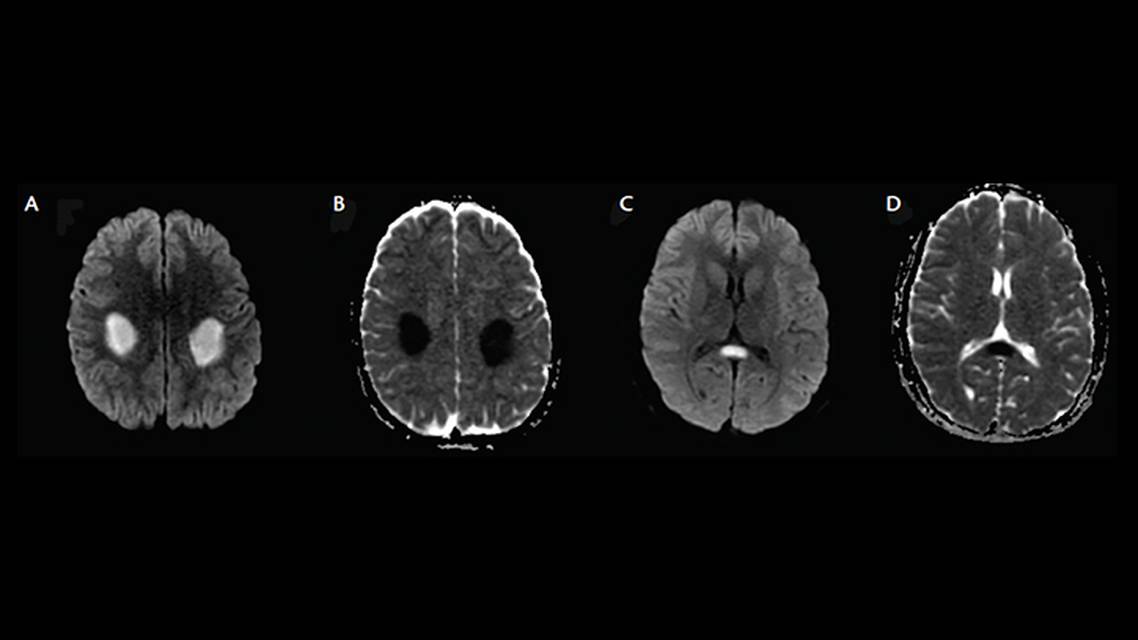

Along with routine hematological and biochemical tests, we obtained lumbar puncture and cerebrospinal fluid (CSF) analysis, brain MRI, brain magnetic resonance angiography (MRA), and an EEG. Analysis of CSF showed normal cell-count, protein, and glucose levels. There was no bacterial growth after CSF culture. Polymerase chain reaction (PCR) of the CSF was negative for common viral infections (eg, enterovirus, Epstein-Barr virus, or human herpes viruses). The EEG result was normal. Biochemical screening results were negative for mitochondrial and lysosomal disorders. Diffusion-weighted MRI (DWI) and apparent diffusion coefficient (ADC) sequences showed symmetric white matter signal alteration with restricted diffusion involving the bilateral centrum semiovale and the splenium of the corpus callosum (Figure 1). Brain MRA results were normal.

Figure 1. Brain MRI at 11 years of age. Diffusion-weighted image sequence (A, C) and apparent diffusion coefficient (B, D) showing restricted diffusion in the centrum semiovale (A, B) and the splenium of the corpus callosum (C, D).